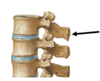

describe LUMBAR vertebrae

(shape, superior/inferior surfaces, and discs)

- shape: kidney bean vertebral bodies

- superior/inferior surfaces of L1-L3 are parallel**, and L4/L5 are **wedge-shaped

- Discs are wedge-shaped and contribute to most typical lumbar curve (lordosis)